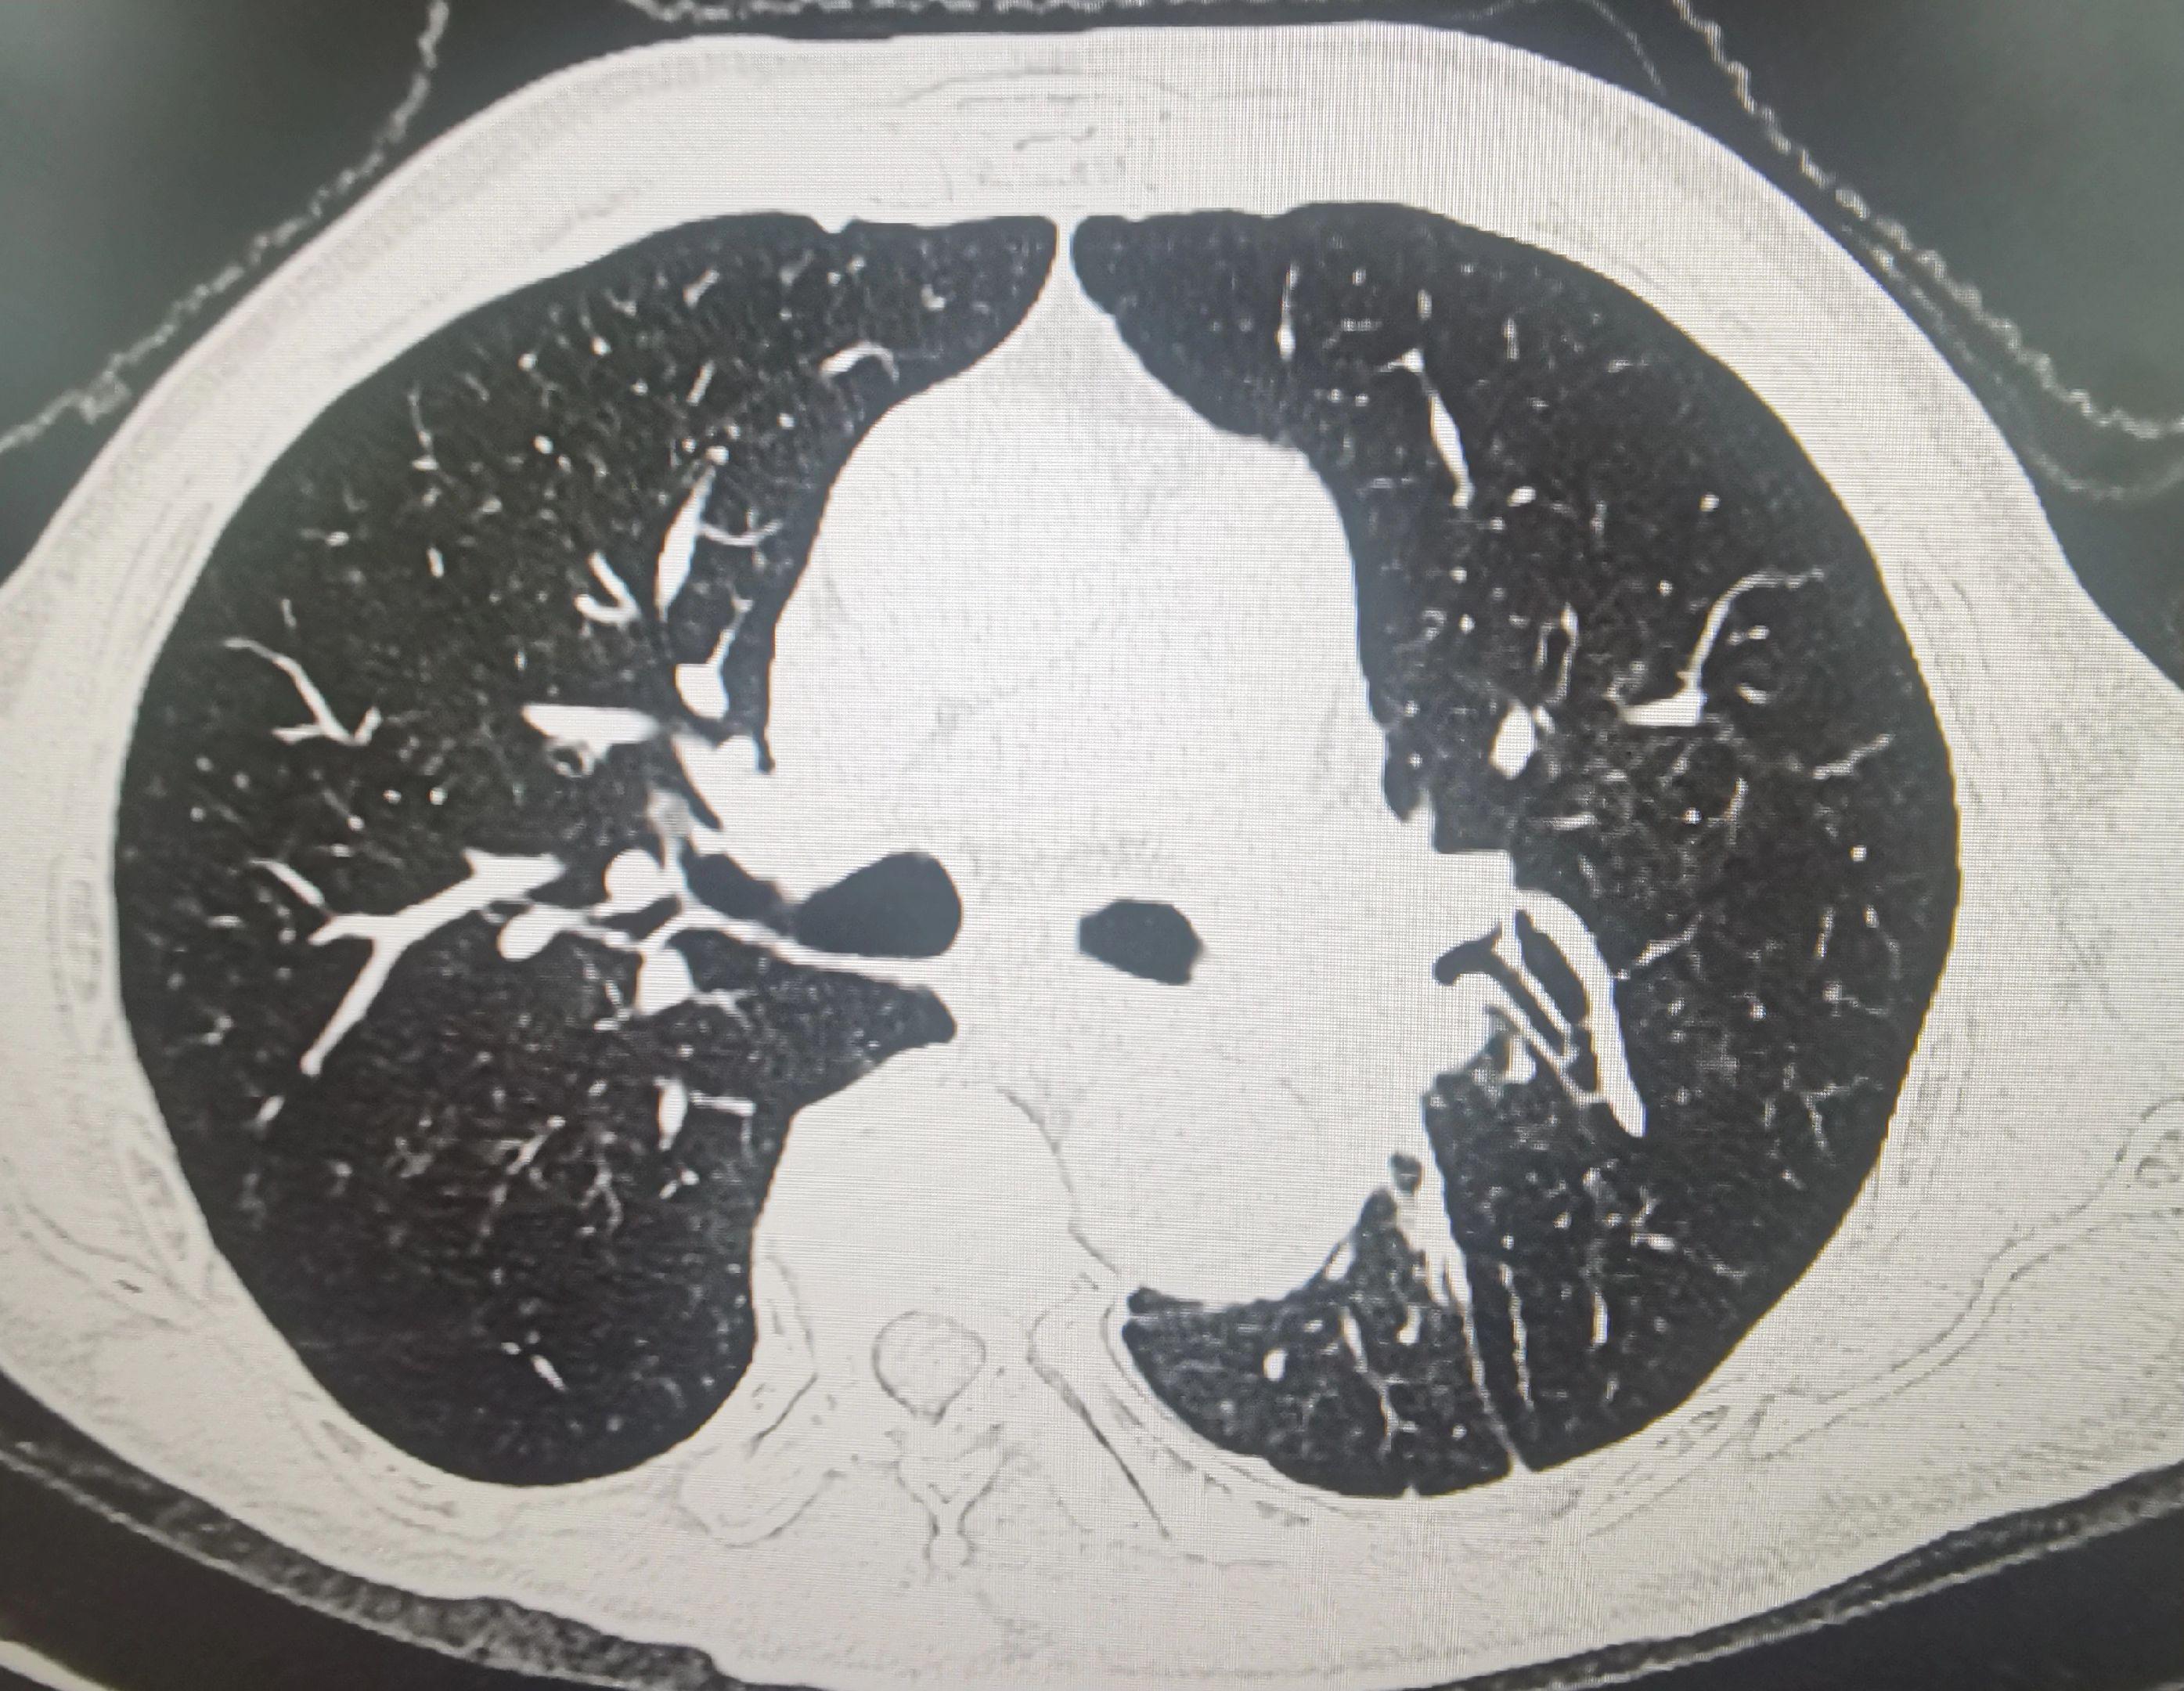

肺癌患者,左肺完全肺不张。经过一次bace的治疗,一个月后复查CT左肺完全复张,为后续全身治疗提供条件